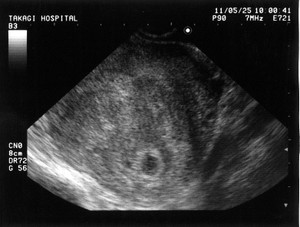

突然ですが、今年の1月初め、我が家の愛犬がお亡くなりになりました。享年2.5歳。ペギニーズとシーズーのMIX。昨年末に歯石を取りに獣医さんに行ったら、麻酔の関係で血液検査。結果は生きているのが不思議なくらいの数値。腎臓の機能がほとんど無い状態。歯石どころではなく、即、治療開始。